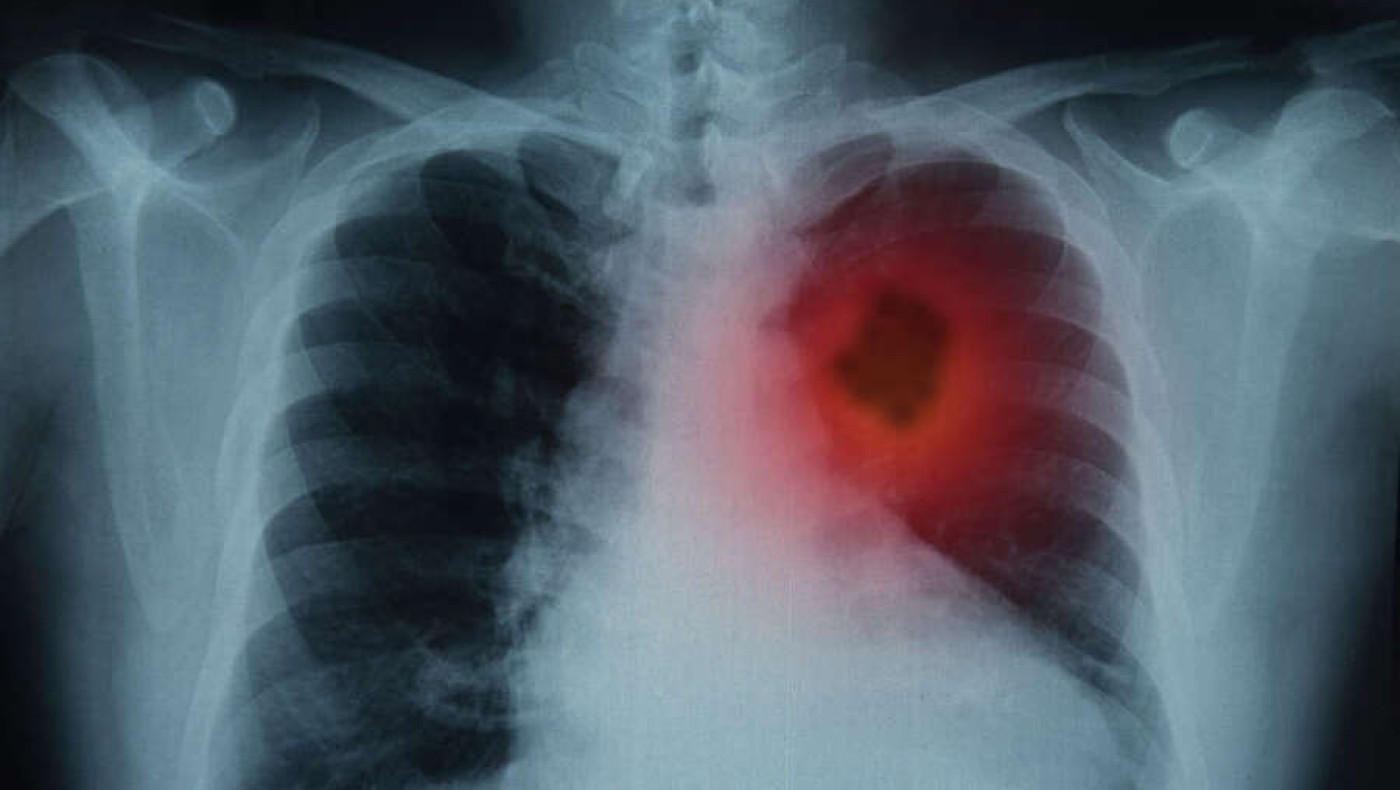

Σύμφωνα με νεότερη μελέτη που δημοσιεύτηκε στο Antioxidants, η φυσική ένωση κατέστειλλε τον πολλαπλασιασμό των καρκινικών κυττάρων του πνεύμονα στο εργαστήριο (in vitro), μειώνοντας παράλληλα τη φλεγμονή των αεραγωγών και τη βλάβη στα υγιή πνευμονικά κύτταρα που εκτίθενται σε χημικές ουσίες από τον καπνό του τσιγάρου.

Αξίζει να αναφερθεί, τέλος, ότι ο καρκίνος του πνεύμονα είναι είναι η κύρια αιτία θανάτων από καρκίνο παγκοσμίως, με περίπου 1,8 εκατομμύρια θανάτους να αναφέρονται ετησίως.